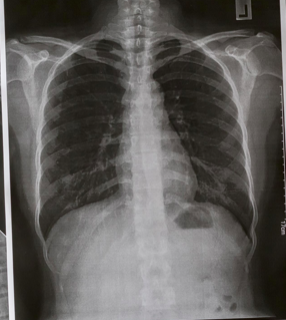

How do you systematically review a chest x-ray?